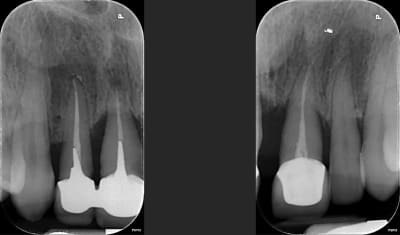

Patiente de 52 ans avec parodontite avancée

mon plan de ttt est le suivant extraction les dents aboluments non conservable (11-21-25) et tenter de garder le reste, puis réévaluer le cas apres surfacage et gingivectomie. Puis de couronner le reste: bridge 13 12 (11 21) 23, couronnes jumélées 14 15 16 17, bridge 24 (25) 26 27.

Ou extraction totale haut, implantation immédiate et mise en charge immédiate (j'adresserai a un implanto pour cela)

Pour le bas ca me parait plus simple, soins 47, surafacage, implant 46 45 35 36 + cr

11 21 et 15 16 sont solidarisées ??

Pour les rétro je trouve qu'elles sont pas nettes... moins nettes que la pano.